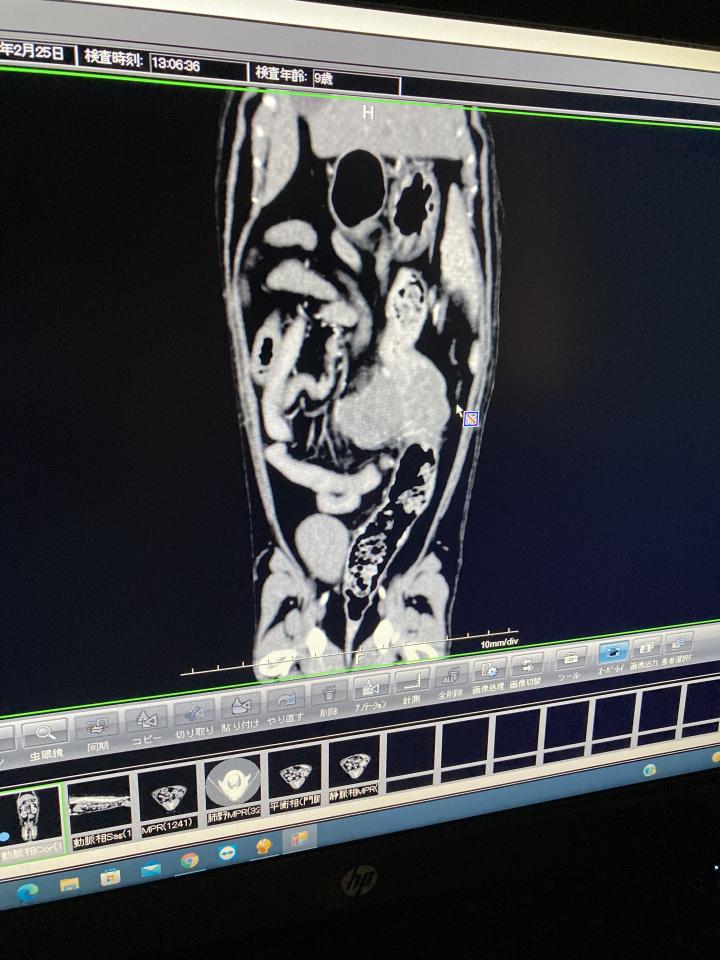

・消化器には腫瘍がある。

ただ、今のところ他の臓器には気になるものはない。

茶々の腫瘍は消化器の表面に出来ている。

なので今のところ大きな症状が出ていないと考えられる。

茶々の場合、消化器の内面にはまだ少ししか腫瘍が出来ていない。

大腸の内面に腫瘍が出来ると、便が出にくくなったり、それに伴い食欲が減退することもあり、重症化しやすい。